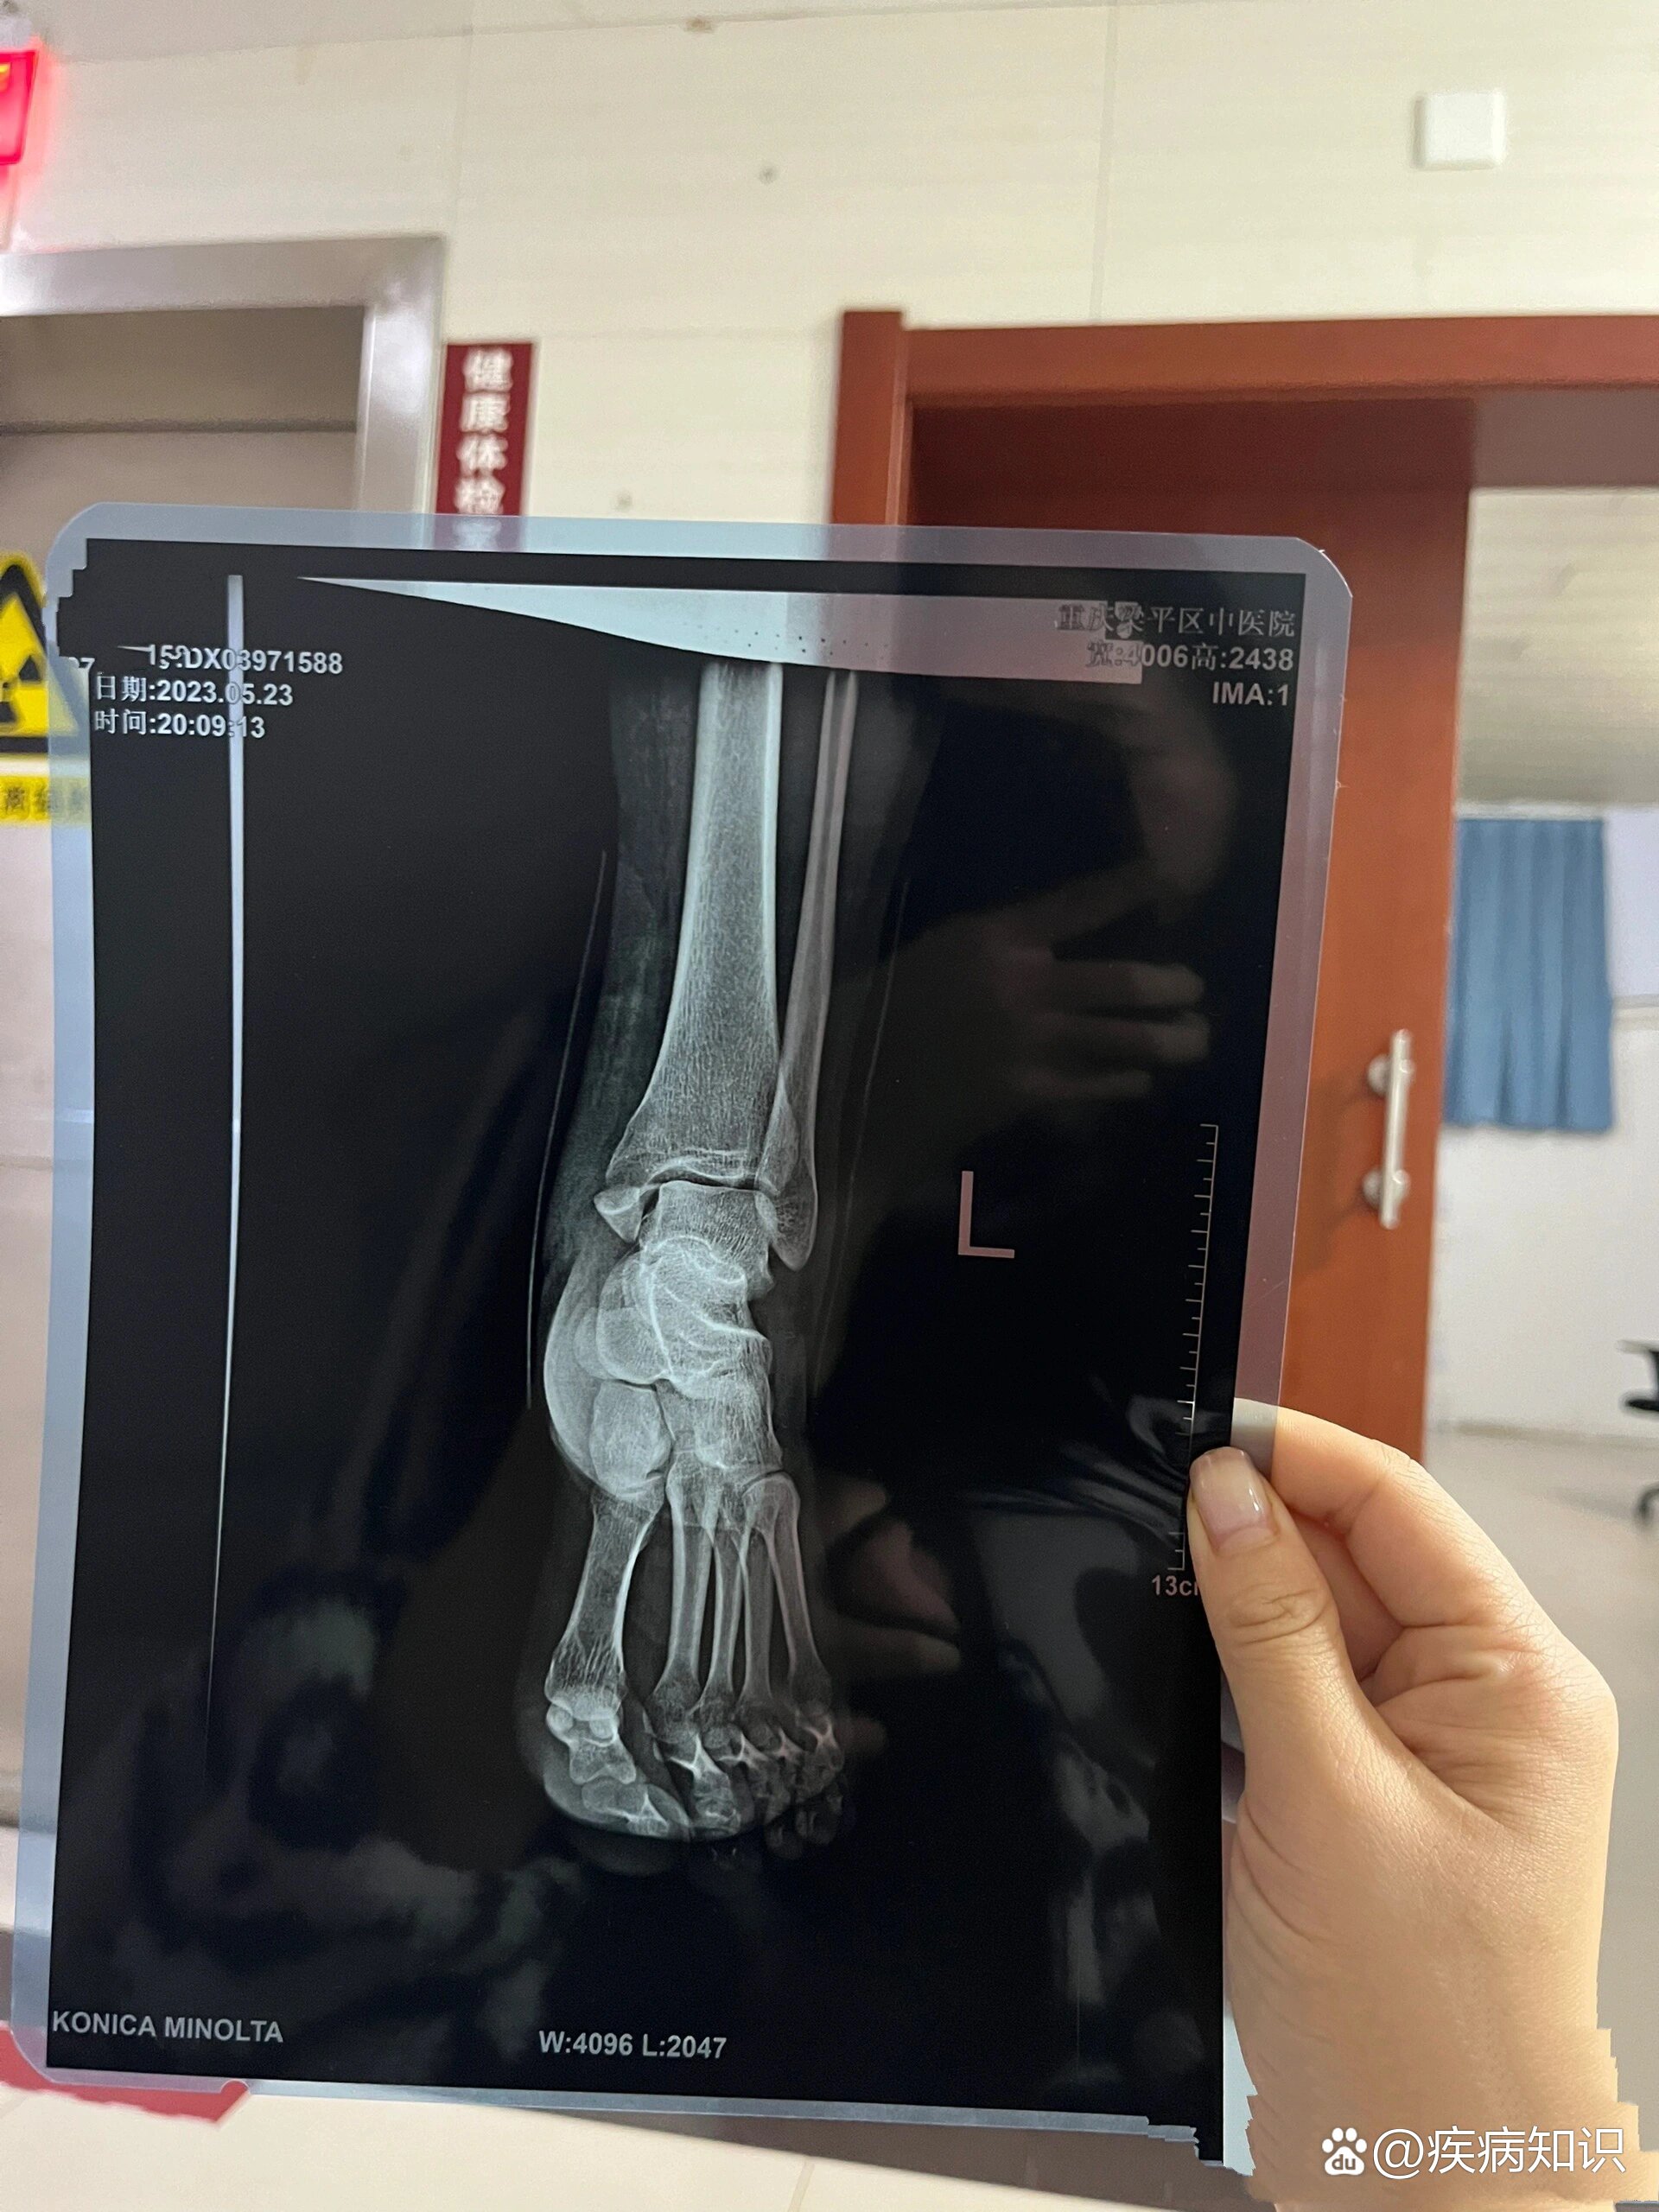

内踝骨折片子